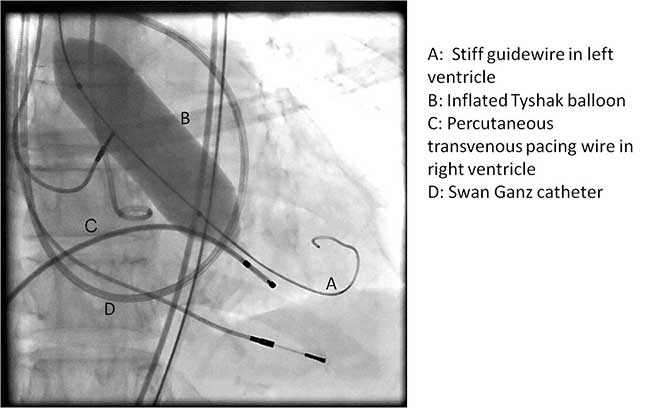

The Sapien valve is a balloon expandable platform and it comes in two sizes, 23 mm and 26 mm. The valve is prepared and mounted onto a sheath system for implantation on the back table. The femoral arterial access is serially dilated to accommodate a 22 French (for 23 mm Sapien valve) or a 24 French (for 26 mm Sapien valve) sheath. The balloon mounted valve is then advanced in a retrograde fashion into the aortic valve position using angiographic and echocardiographic guidance (Figure 2). It is important to visualize the position of the valve using at least 2 different angles. For the transfemoral approach, the recommended positioning of the prosthesis is 60%-40%, which is 60% of the prosthesis should be on the ventricular side of the aortic annulus with 40% of the prosthesis on the aortic side of annulus. This is due to the past experience observation that the prosthesis has a tendency to migrate in the aortic direction during deployment. This phenomenon is likely a result of the stored torque in the delivery system when introduced from the femoral artery. For ease of prosthesis arch transit, the delivery platform is equipped with the Retroflex system from Edwards. Of note, the correct orientation of the prosthesis should be confirmed both visually prior to placement into the introducer sheath and angiographically prior to deployment. Next, transvalvular flow is severely depressed by rapid ventricular pacing. The valve is then balloon expanded rapidly and implanted in position. If there is moderate to severe aortic insufficiency from a paravalvular leak after the deployment, a second ballooning with a larger volume is performed under conditions of rapid ventricular pacing.